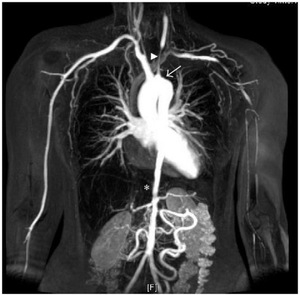

- Angiography revealing narrowing/occlusion of large vessels (e.g. Aorta) is the gold standard [3]

- MRA or CTA can be used as well to appreciate vascular stenoses